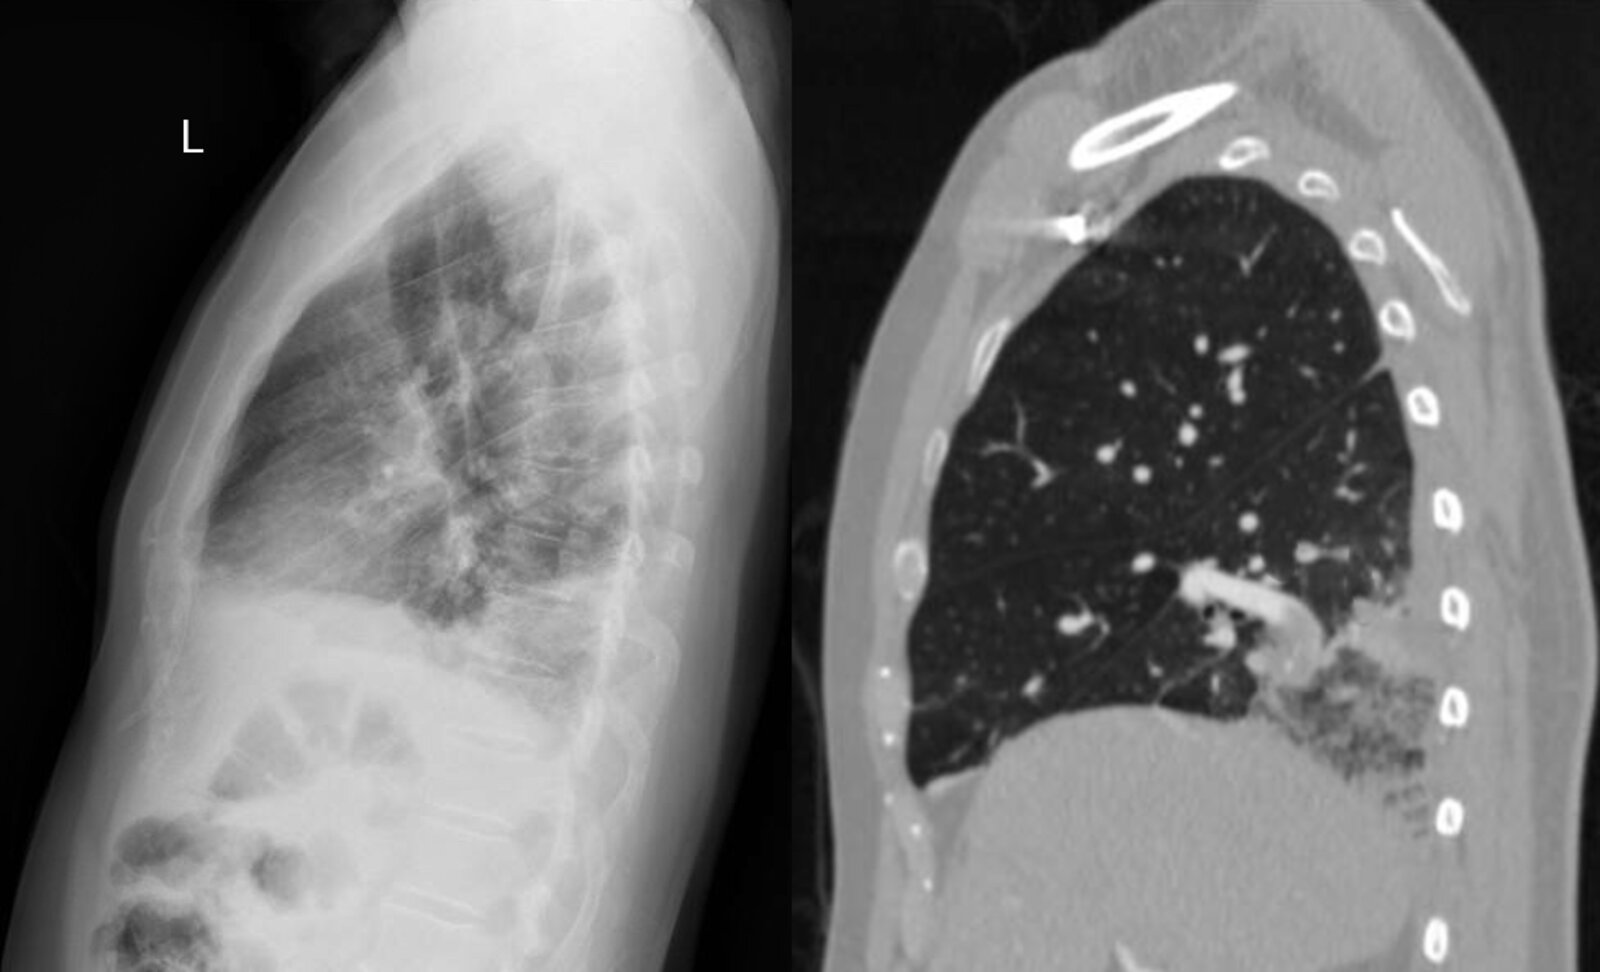

Spontaneous pneumothorax [22][25][26]

• Sudden, sharp unilateral chest pain

• Acute dyspnea

• Hypoxemia

• Hyperresonance on percussion, decreased breath sounds on the affected side

• Crepitus

• History of lung disease or trauma

• Inspiratory CXR: increased lucency, displaced lung markings, subcutaneous emphysema

• POCUS: absent lung sliding on eFAST or lung POCUS

• See β€œAcute management checklist for spontaneous pneumothorax.”